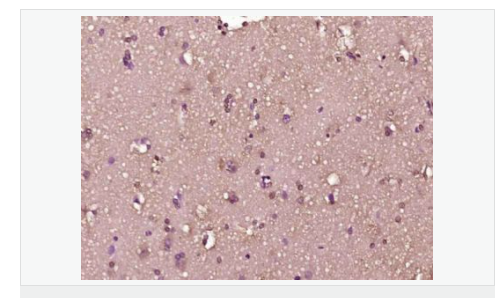

交叉反应:Human,Mouse,Rat(predicted:Dog,Pig,Cow) 推荐应用:IHC-P,IHC-F,IF,ELISA

| 产品应用 | ELISA=1:5000-10000 IHC-P=1:100-500 IHC-F=1:100-500 IF=1:100-500 (石蜡切片需做抗原修复) not yet tested in other applications. optimal dilutions/concentrations should be determined by the end user. |